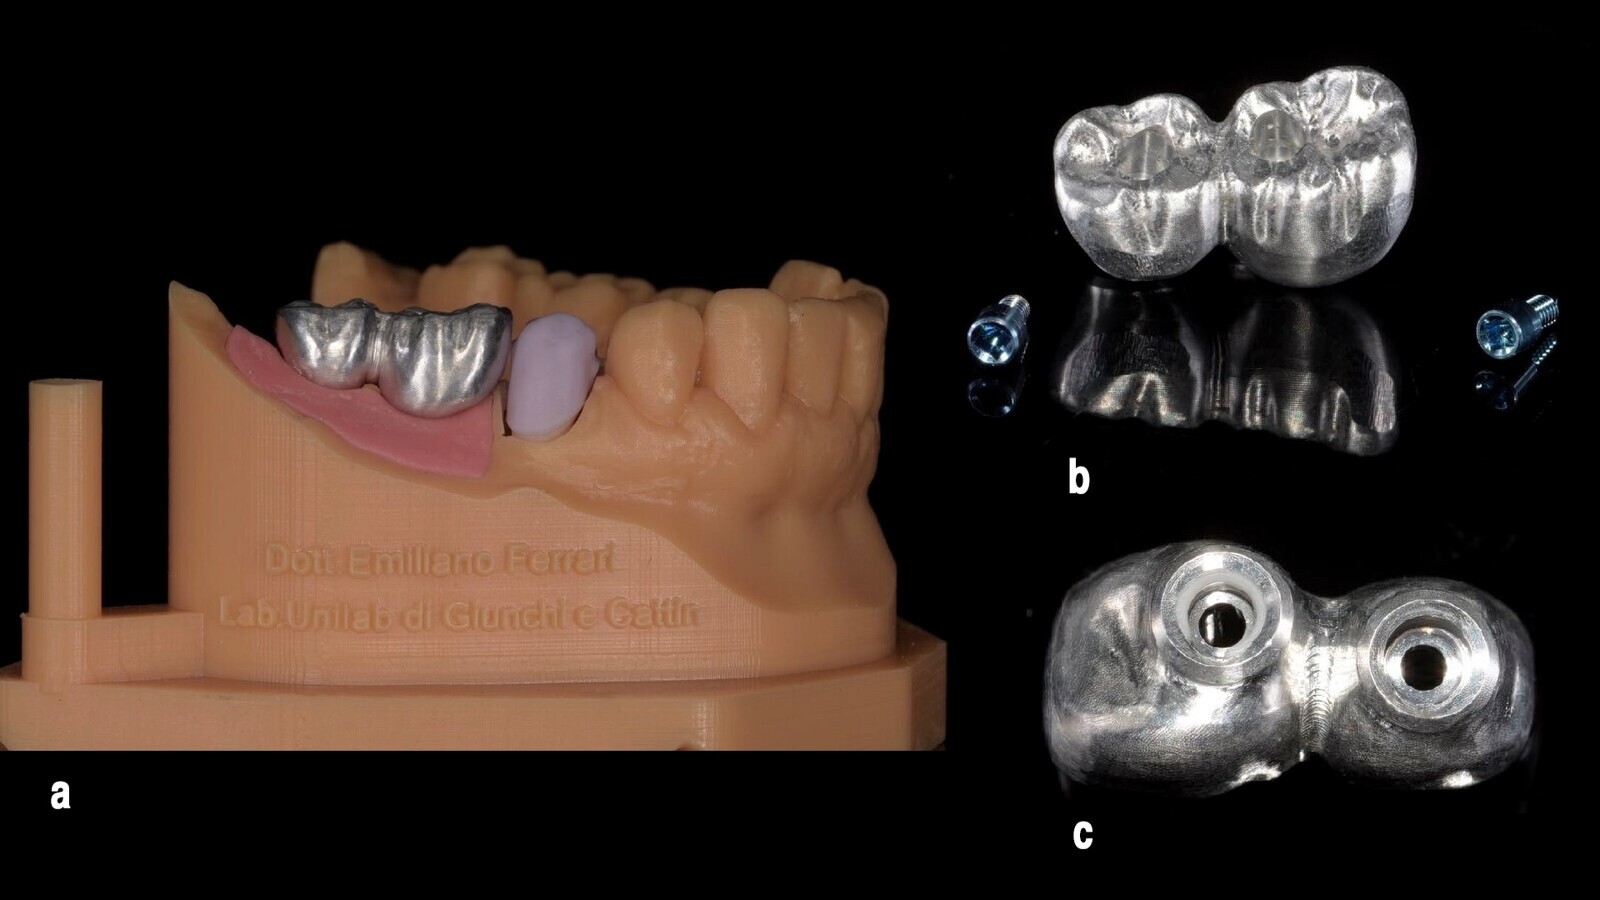

Figura 5. Mediante la "lectura" del antiguo pilar, fue posible identificar el paso de rosca y la plataforma del implante (5a) para obtener, además del kit mencionado, dos pilares Equator de OT personalizados (5b).

Figura 14. El modelo maestro se realizó utilizando los análogos del Equator de OT y se escaneó, como se observa en estos dos ángulos.

Figura 15. El escaneado permitió la confección del provisional mediante técnica digital.